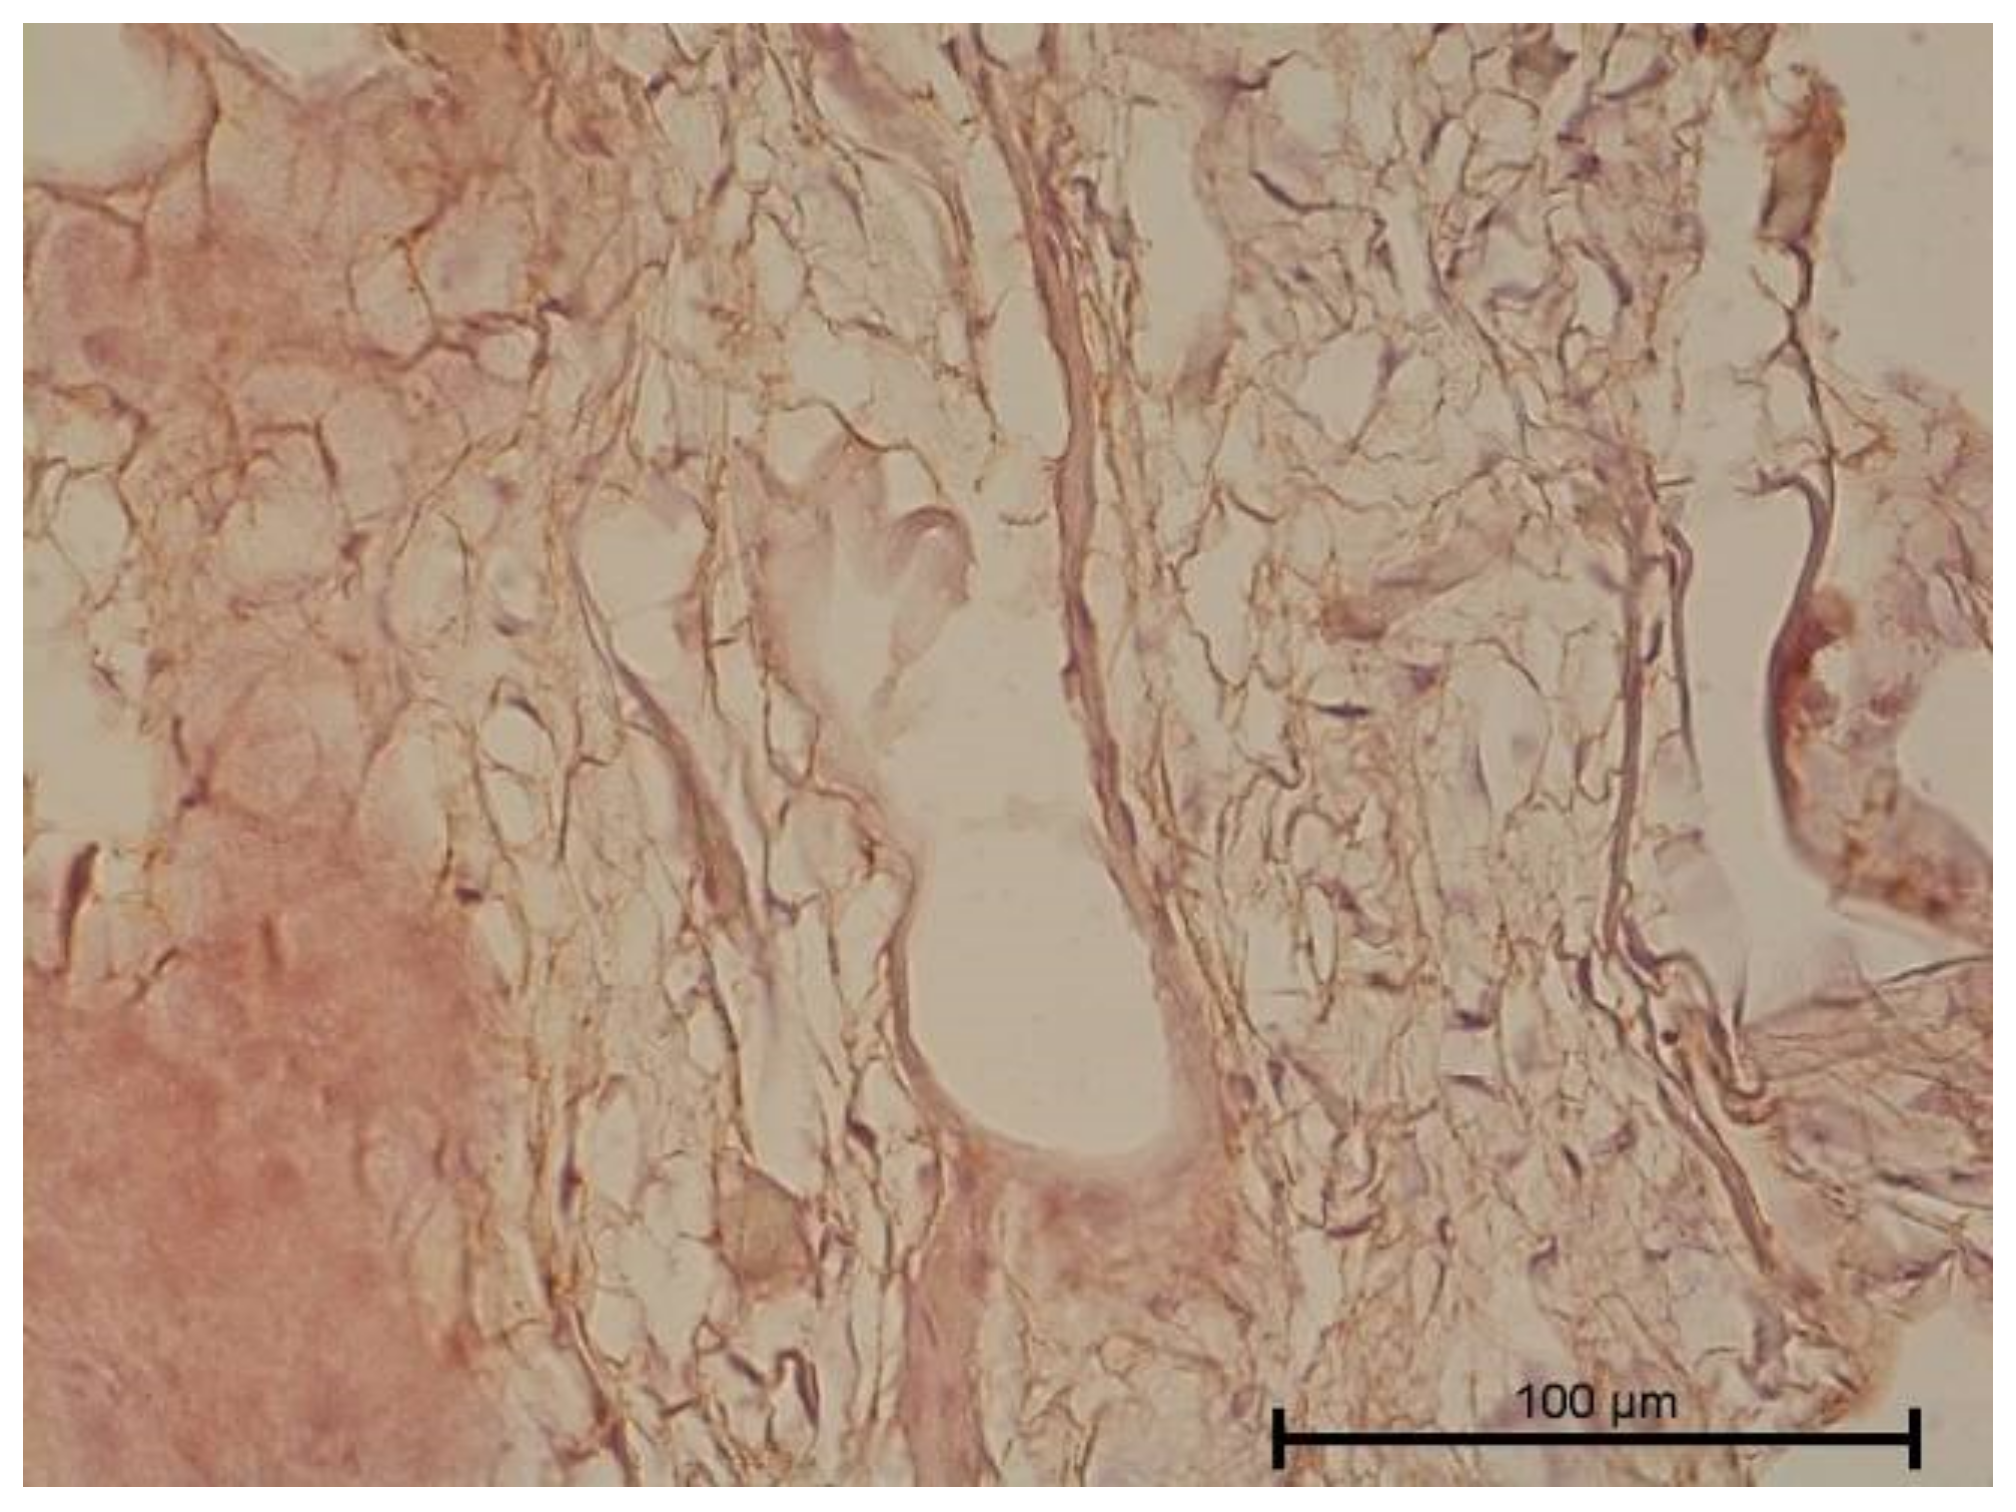

4.3. Immunohistochemical Examination

5. Discussion